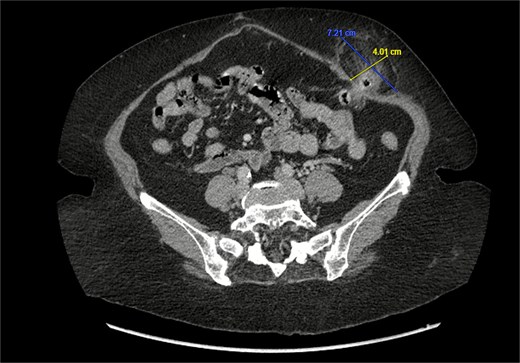

A 76-year-old female with a medical history of type 2 diabetes mellitus (controlled with oral medications), hypertension (on two medications), hyperlipidemia (on atorvastatin), and recently diagnosed Alzheimer’s disease (started on memantine) presented to the emergency department with severe left-sided abdominal pain of 2 days’ duration. The pain began gradually but worsened significantly in the last few hours. It was associated with a bulging mass in the abdomen that was tender and painful to touch. The patient reported that the swelling had been present for 2 years, intermittently reducible with minimal exertion. However, since the previous day, it had become irreducible and increasingly painful, particularly after a failed attempt to reduce it manually at home. She also admitted to chronic constipation for years, usually treated with oral laxatives, though she had not been compliant with them recently. Her surgical history included a laparoscopic cholecystectomy combined with paraumbilical hernia repair using mesh 3 years ago. Upon examination by the on-call surgical team, the patient was afebrile with stable vital signs. Her abdomen was distended, and a 7 × 7 cm irreducible, tender mass was noted over the left side. An urgent computed tomography (CT) scan of the abdomen and pelvis with intravenous and oral contrast revealed a left lateral ventral abdominal hernia traversing the left lateral oblique muscles. The hernia sac contained omental fat and an inflamed diverticulum of the transverse colon, with surrounding inflammatory changes. The defect measured 1.4 × 1 cm, and the hernia sac measured 6.7 × 4.2 × 4 cm. No free fluid, fluid collections, or pneumoperitoneum were identified (Figs 1–3).

Coronal section of CT abdomen and pelvis showing the ventral hernia.